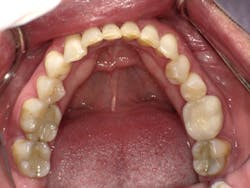

Maxillary arch prior to restorative treatment